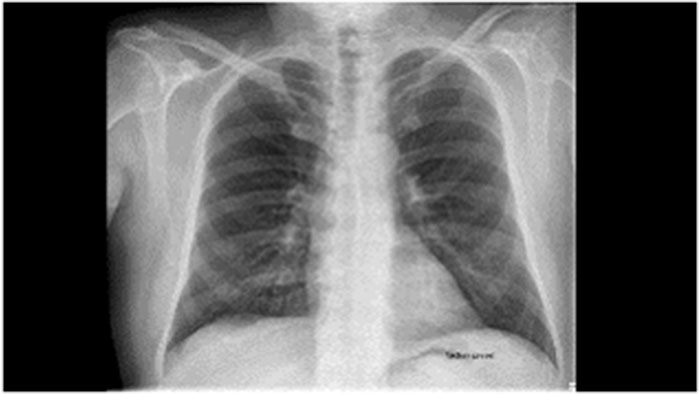

Clinicians often desire to view a patient's X-ray and fluoroscopy studies along with images from CT/MR/MI/US. Radiologists and clinicians who want to review a patient’s MR or CT study may also be required to view their prior or recent X-rays or fluoroscopy studies to understand the pathology well or progression of the disease. It is important to provide a platform to review of various patient studies in a common platform so radiologists can get a comprehensive review environment.